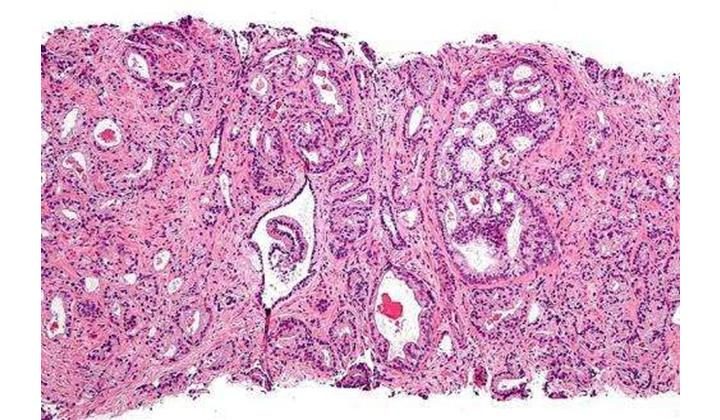

Ингибитор PARP Олапариб (Lynparza®) одобрен в ЕС в качестве монотерапии для поддерживающего лечения у пациентов с высокосортной серозной эпителиальной карциномой яичника, карциномой фаллопиевой трубы или первичной карциномой брюшины, независимо от статуса BRCA, если они реагируют на химиотерапию на основе платины (полный или частичный ответ) .

Olaparib, sold under the brand name Lynparza, is a medication for the maintenance treatment of BRCA-mutated advanced ovarian cancer in adults .It is a PARP inhibitor, inhibiting poly ADP ribose polymerase (PARP), an enzyme involved in DNA repair .It acts against cancers in people with hereditary BRCA1 or BRCA2 mutations, which include some ovarian, breast, and prostate cancers .